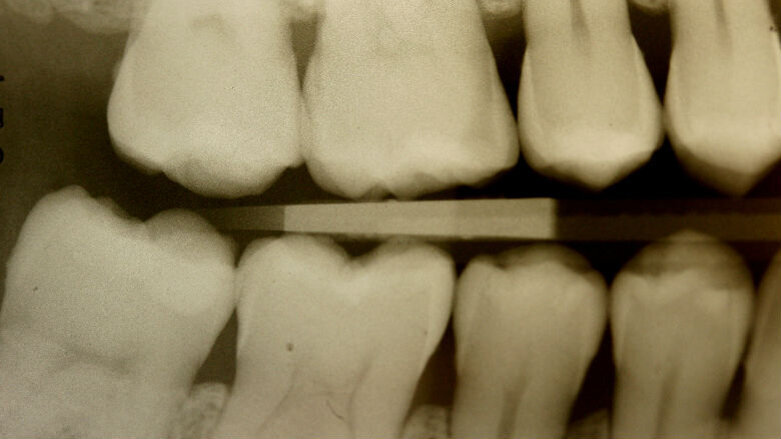

La paziente, FF di anni 38, è giunta alla mia osservazione per la cura delle lesioni cariose presenti. All’esame obiettivo non erano evidenti lesioni cariose di notevole entità (Figg. 1, 2): solo attraverso le bite-wing (Figg. 3, 4), mezzo indispensabile per la diagnosi odontoiatrica in conservativa, si evince la presenza di numerose lesioni cariose coinvolgenti il tessuto dentinale. La paziente richiedeva il raggiungimento di un risultato estetico ottimale, ovvero la mimetizzazione del materiale composito con il tessuto smalteo; oltre a questa esigenza si doveva unire quella di effettuare una riabilitazione funzionale ovvero, trattandosi del settore posteriore, che sopportasse il carico masticatorio garantendo la minima usura possibile nel tempo. Alla paziente è stato proposto un piano di trattamento che prevedeva la cura diretta delle lesioni cariose suddivise per quadranti e la riabilitazione indiretta dell’elemento 47 in modo da permettere la migliore precisione marginale garantendo un ottimo follow-up a lungo termine. Si è proceduto con la riabilitazione mediante il composito di recente introduzione Enamel Plus HRi Bio Function (Micerium, Avegno, Genova). Bio Function è disponibile in 3 smalti: BF1 basso valore - BF2 medio valore - BF3 alto valore e in 9 dentine: BD0 - BD0,5 (per restauri di denti particolarmente bianchi o sbiancati) BD1 (A1 Scala Vita) - BD2 (A2 Scala Vita) - BD3 (A3 Scala Vita) - BD3,5 (A3,5 Scala Vita) - BD4 (A4 Scala Vita) BD5 - BD6.

Fig. 3_Bite-wing di destra.

Fig. 4_Bite-wing di sinistra.